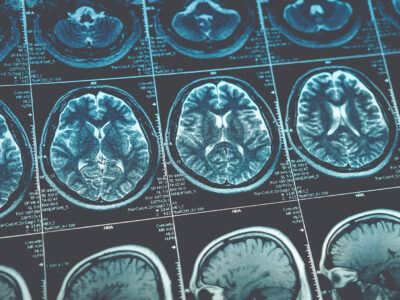

Head injuries, including concussions, vary in severity. Some might be minor and only require observation, but others can be life-threatening and require immediate medical attention. Loss of consciousness, severe headache, vomiting, slurred speech and neurological deficits are signs of a serious injury requiring emergency care.